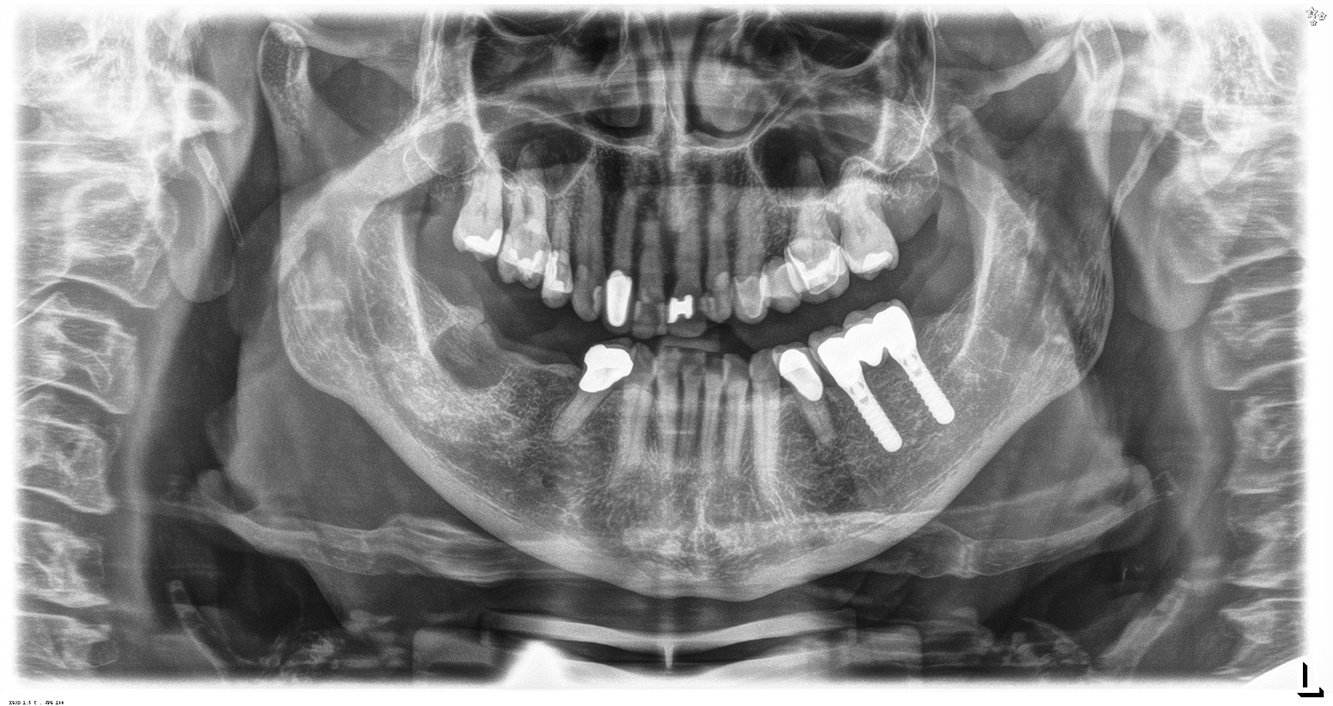

La paciente de 68 años no tiene enfermedades previas relevantes de la salud general ni toma medicación; sus hábitos alimentarios tampoco suponen un riesgo especial. La paciente tiene dos implantes (tercer cuadrante, desde hace cinco años) y una enfermedad previa periodontal (periodontitis en etapa IV, grado B) con pérdida dental. Actualmente las condiciones periodontales son estables, pero la periodontitis aumenta de manera determinante las complicaciones biológicas cuando se realizan implantes y puede ocasionar la pérdida de un implante (21). Para la sesión de profilaxis se hacen cuatro recomendaciones.

Al seleccionar el instrumental, se aplica un procedimiento especial en la zona de los implantes. Para conservar la superficie del implante y, al mismo tiempo, limpiarla con eficacia, es crucial seleccionar los instrumentos y los polvos adecuados, como el uso dirigido de aeropulidores con puntas Paro especiales. La elección de los polvos adecuados puede hacerse según las necesidades y los riesgos, por ejemplo, además del grado apropiado de abrasión, pueden tenerse en cuenta los requisitos alimenticios (como que sean sin azúcar o bajos en sal).

Debido a la situación del implante con la enfermedad periodontal previa, la paciente tiene riesgo de desarrollar periimplantitis; se recomienda un intervalo de recuperación de tres a cuatro meses.